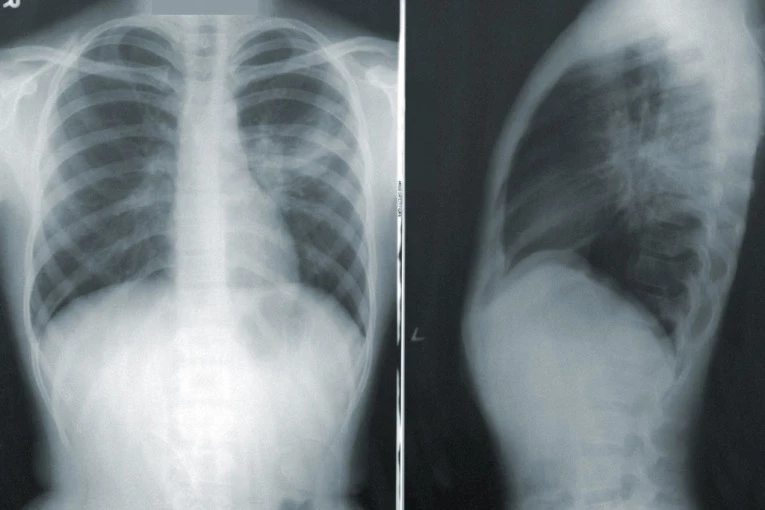

- Možda ste videli te teške slike iz crvenih zona gde pacijente okreću na stomak. Za to treba da bude izuzetno obučen tim, posebno ako je pacijent intubiran. Zašto se to radi? Zato što se na taj način zadnji delovi pluća na koje kada se leži na leđima naležu srce i drugi organi budu manje ventilirani i ishranjeni - navodi Stefanović.

- Svaka virusna infekcija, pa i kovid zahteva mirovanje. Ako se lečite u kućnim uslovima potrudite se da najviše vremena provedete u polusedećem položaju i spavate na stomaku. Na taj način se ventiliraju i oni delovi pluća koji su inače pod pritiskom. To je put do bržeg ozdravljenja - objasnila je Stefanović.